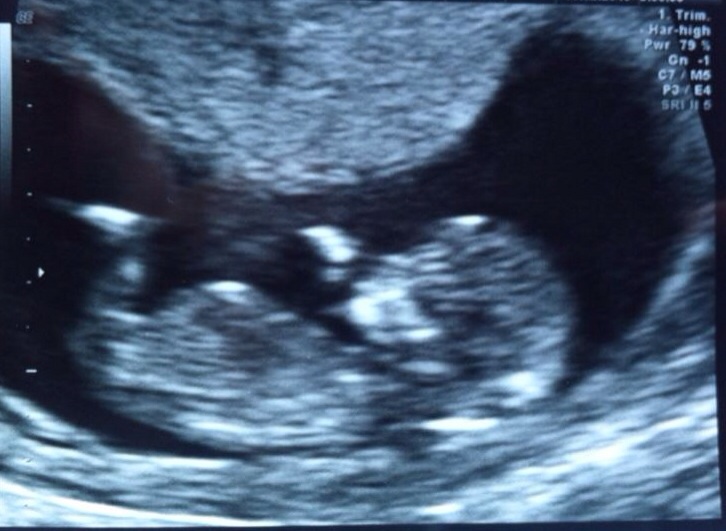

Hi ladies, my friend wants to join the great world of nub guessing. She is measuring 13 weeks. Thanks for any guesses.

Attachment 23725

It's a little busy down there but I'm going to lean pink.

It was a girl...sadly passed away in the womb from a heart defect :(

They found out at her 20 week scan. The baby died two weeks later from its own defect. She is totally gutted. This is also her second loss as 1st baby had no heartbeat at 12 week scan so was a missed miscarriage. She has great support but feels totally depressed. I'm hoping she finds inner strength to get through this.